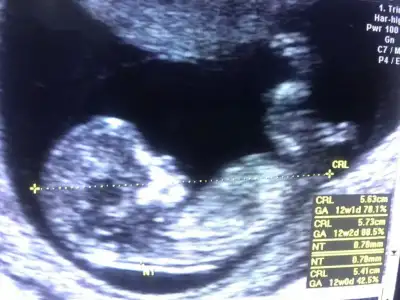

Evet kız görünüyor11 haftalık banada tahmin yapar mısınız arkadaşlar doktor %70 kız dedi sizce nedir . 1oğlum var buda kız olursa çok mutlu olurum

Eki Görüntüle 2806425

Teşekkür ederim cevap için. Hadi inşallahEvet kız görünüyor![]()